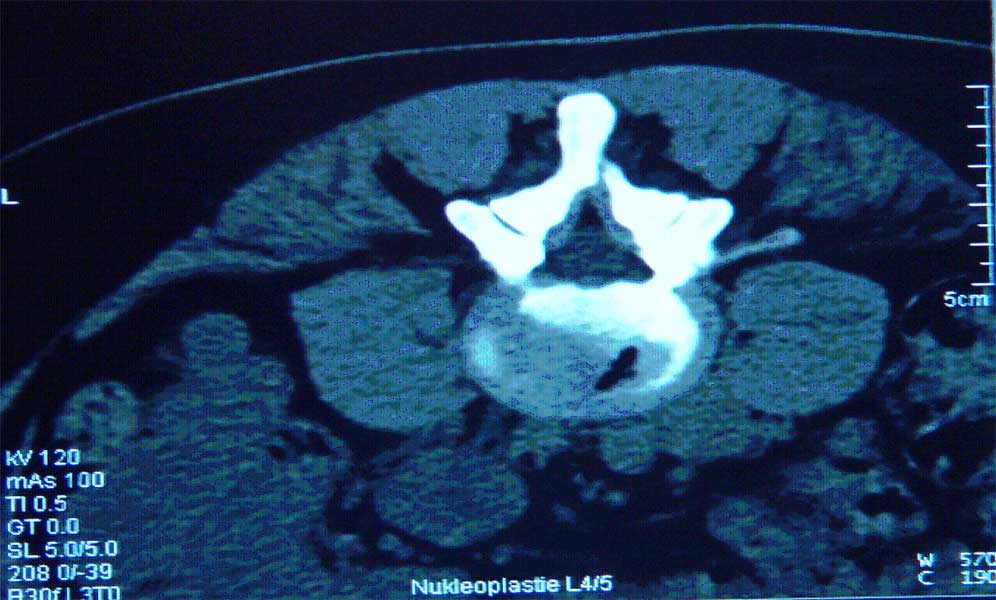

Abb. 1 und 2 von links

Percutaner Zugang zur Bandscheibe

Das Ergebnis der Nucleoplastie ist, postoperativ 5 Minuten später im CT sichtbar.